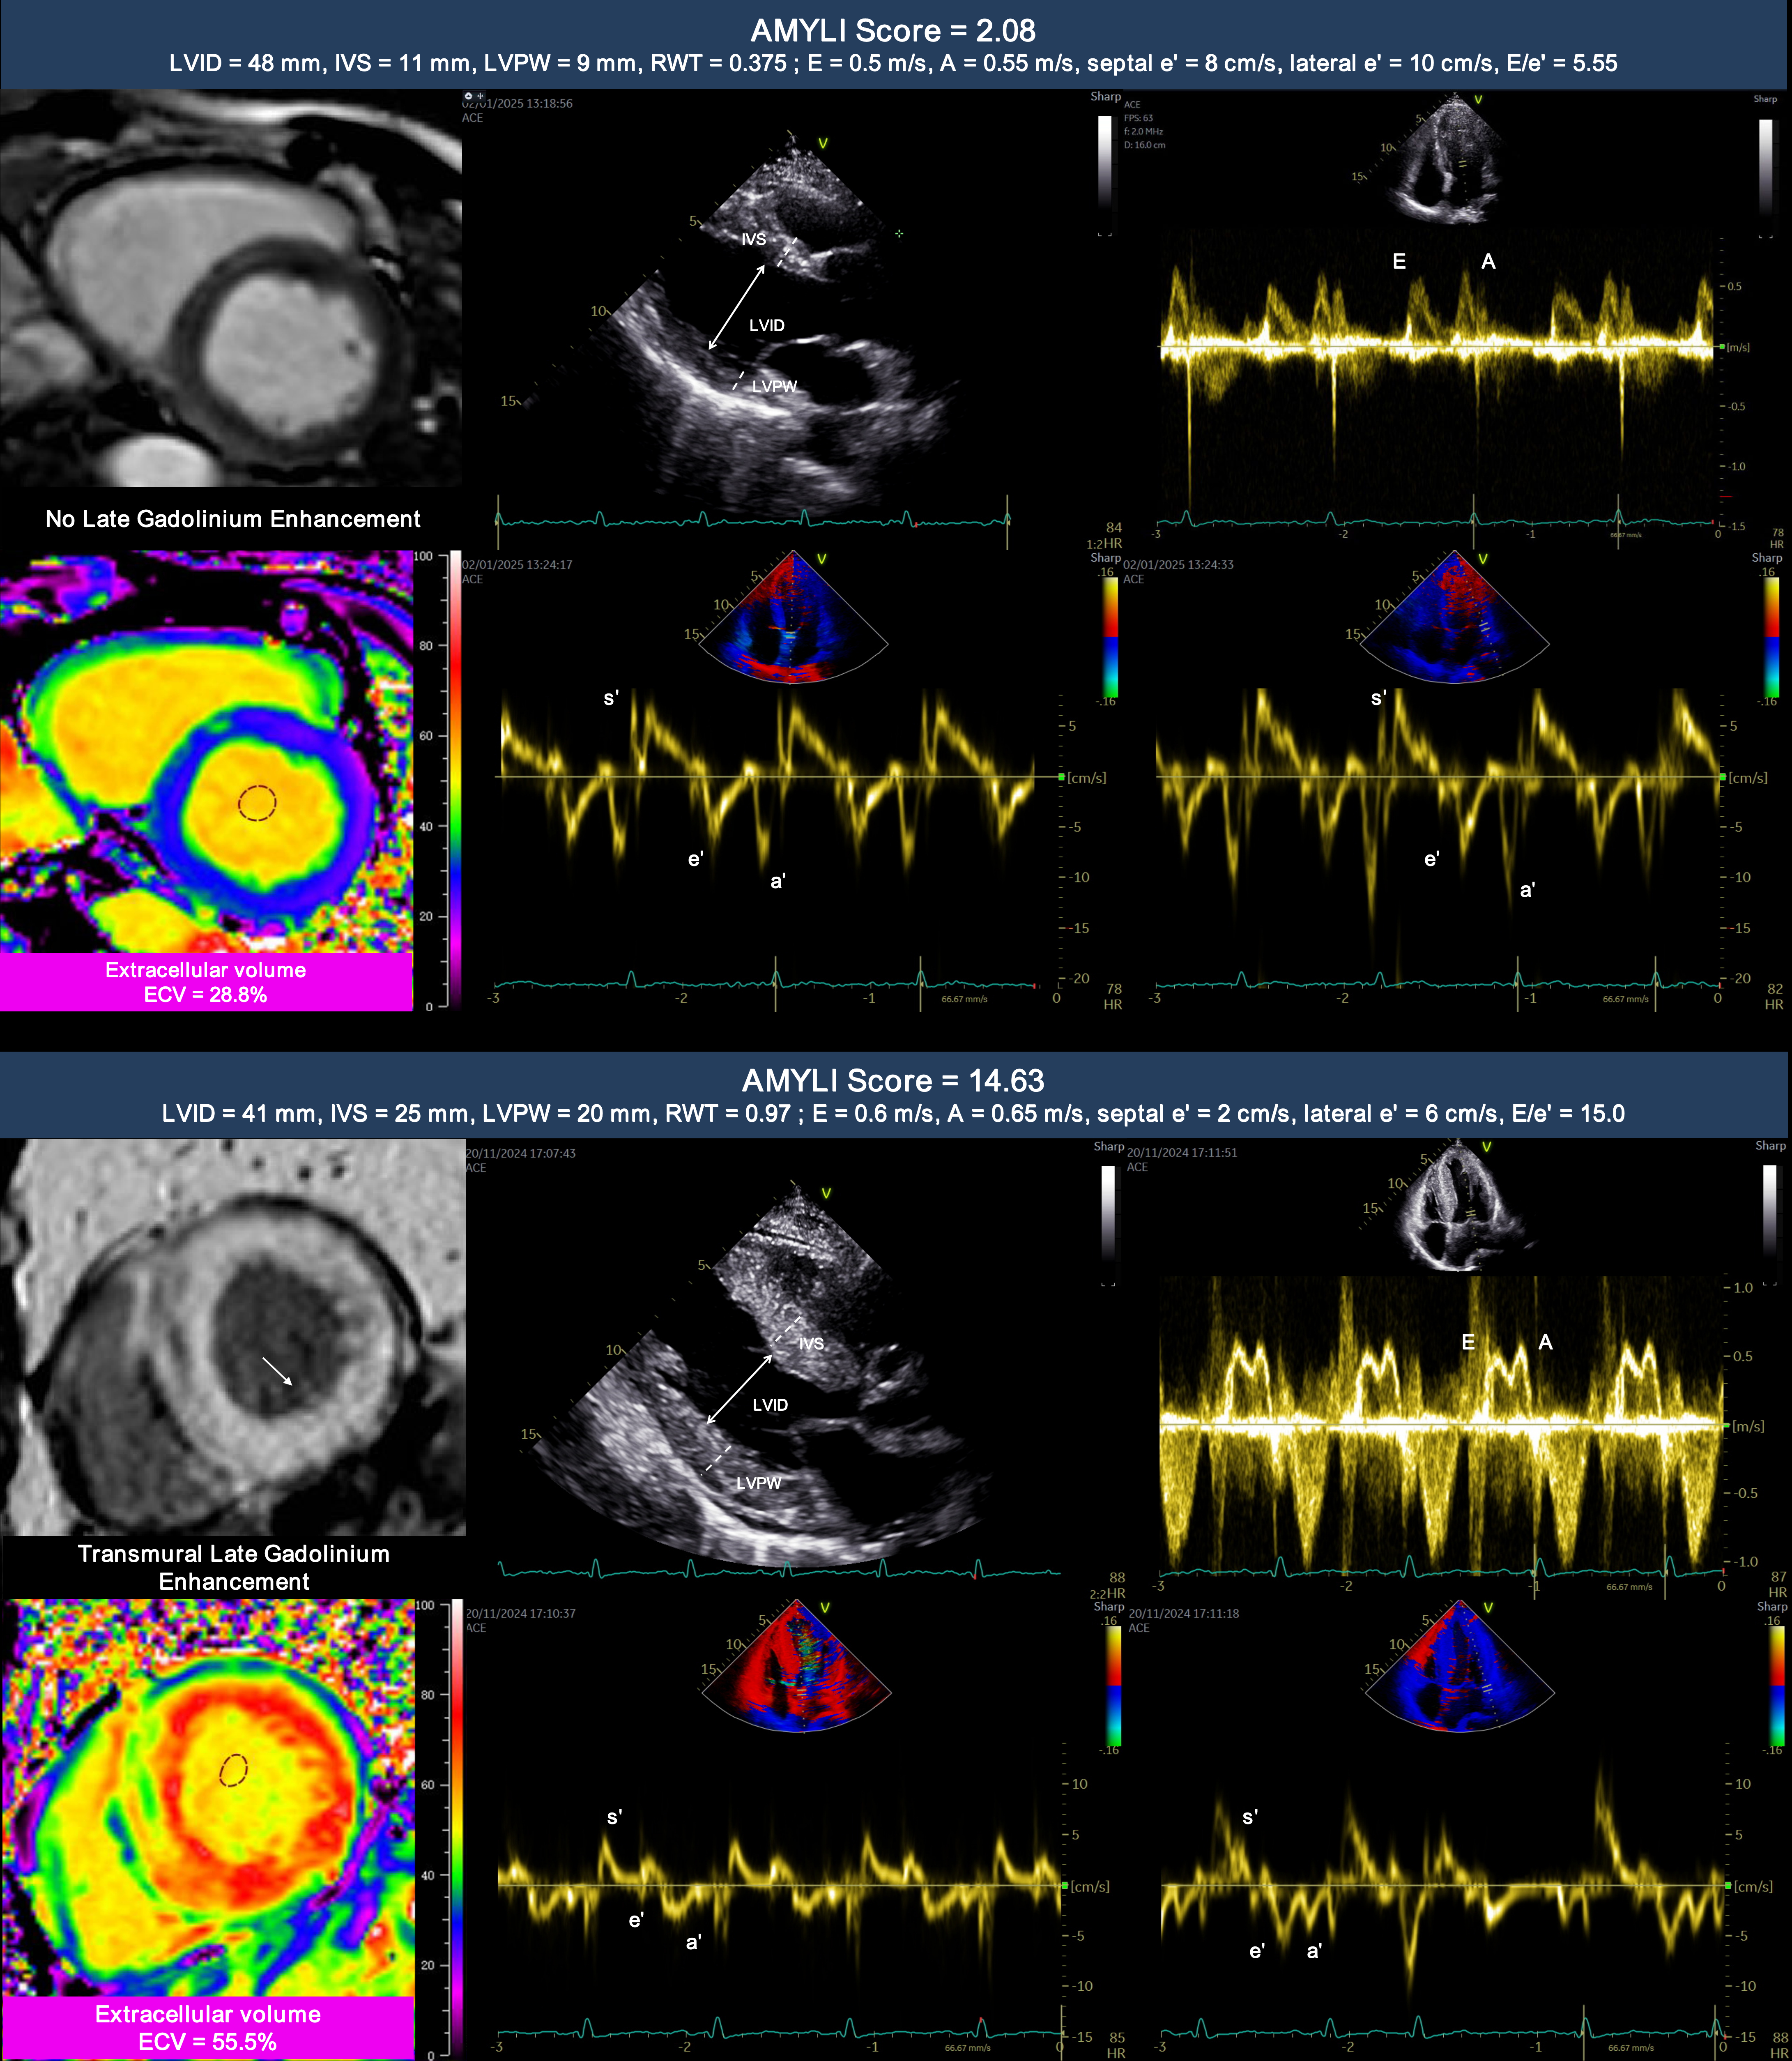

Echocardiographic AMYLI Score in Systemic Light-Chain Amyloidosis: Clinical Relevance and Risk Stratification

Methods: This single-center, prospective, observational study was conducted at West China Hospital, Sichuan University, from November 2011 to September 2023. A total of 307 newly-diagnosed biopsy-proven AL amyloidosis patients who underwent both echocardiography and cardiac magnetic resonance (CMR) imaging were enrolled. The AMYLI score was calculated via transthoracic echocardiography as the product of relative wall thickness (RWT) and E/e′. Lastly, parameters reflecting amyloid burden, such as late gadolinium enhancement, and extracellular volume (ECV), were calculated via CMR.

Results: The AMYLI score exhibited a moderately positive correlation with CMR parameters associated with amyloid burden (ECV; r = 0.57, P < 0.001). During a median follow-up of 42 (interquartile range: 35-49) months, 173 patients died. Meanwhile, an AMYLI score ≥ 7.85 demonstrated a strong predictive value for all-cause mortality [hazard ratio (HR) 2.80, 95% confidence interval (CI): 1.80-4.35, P < 0.001]. After adjusting for clinical (HR 2.01, 95% CI: 1.28-3,16, P = 0.001), biochemical (HR 1.64, 95% CI: 1.03-2.61, P = 0.026), echocardiographic (HR 1.99, 95% CI: 1.24-3.17, P = 0.002), CMR imaging-related (HR 1.92, 95% CI: 1.11-3.33, P = 0.014), and therapeutic (HR 1.79, 95% CI: 1.14-2.82, P = 0.007) factors, an AMYLI score ≥ 7.85 remained an independent prognostic factor. AMYLI score ≥ 7.85 added incremental prognostic value to conventional clinical and imaging risk factors.

Conclusions: The AMYLI score is a reliable indicator of amyloid burden in patients with CA and possesses independent prognostic value, offering an alternative and convenient echocardiography-based imaging marker for the risk stratification of CA patients.